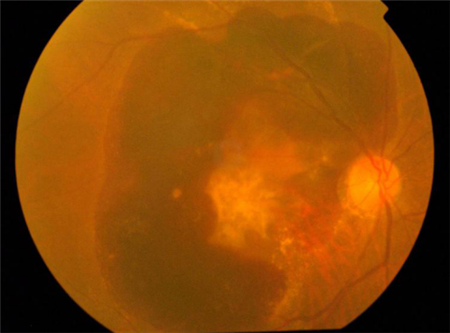

而濕性黃斑變性,其成因是脈絡膜出現了非正常的新生血管,這些新生血管很容易發生滲漏和出血。若未及時治療,滲出物及血液會聚集與黃斑區,并破壞區域內的感光細胞,對視力造成極大威脅。

與惡化緩慢的干性黃斑病變不同,濕性黃斑病變惡化速度非常快,癥狀也較為明顯,表現為視物變形、中心視力下降、視野中心有暗點等癥狀。若出現這些癥狀,需立即就醫,否則可能造成不可彌補的視力受損。